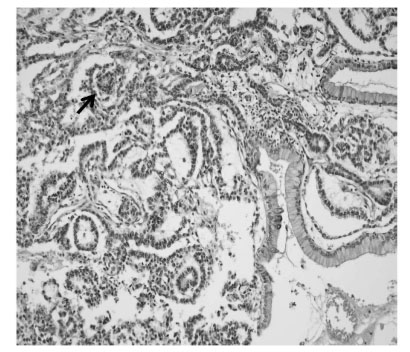

Fig 1). An explorative laparotomy revealed a 9 × 8 cm, globular encapsulated mass, located between the greater omentum and transverse mesocolon, and a 1 cm, ovoid nodule in segment IV of the liver. The mass showed no evidence of invasion of adjacent organs. Both ovaries were normal at the time of surgery. The mass was completely excised surgically, and the hepatic lesion underwent wedge resection. Grossly, the tumor was a 10 × 9 cm, whitish to gray, globular solid mass (

Fig. 2); sectioning revealed semisolid grayish material and cartilaginous tissue. Pathologic examination revealed a mixed malignant GCT made of two components, a mainly endodermal sinus tumor and a small mature teratoma. We also observed a loose reticular pattern and rounded papillary processes with central capillary, Schiller-Duval bodies. The tumor was immunohistochemically positive for AFP. The resected hepatic specimen was a metastasis of the mixed GCT and was histologically identical to that component of the primary tumor (

Fig. 3Microscopic examination, showing that the primary tumor was composed primarily of endodermal sinus tumor components. A loose reticular pattern and rounded papillary processes with central capillary, "Schiller-Duval bodies" were also observed (arrow). The section from the liver shows a metastatic germ cell tumor, composed primarily of an endodermal sinus tumor component (H & E, × 200 magnification).